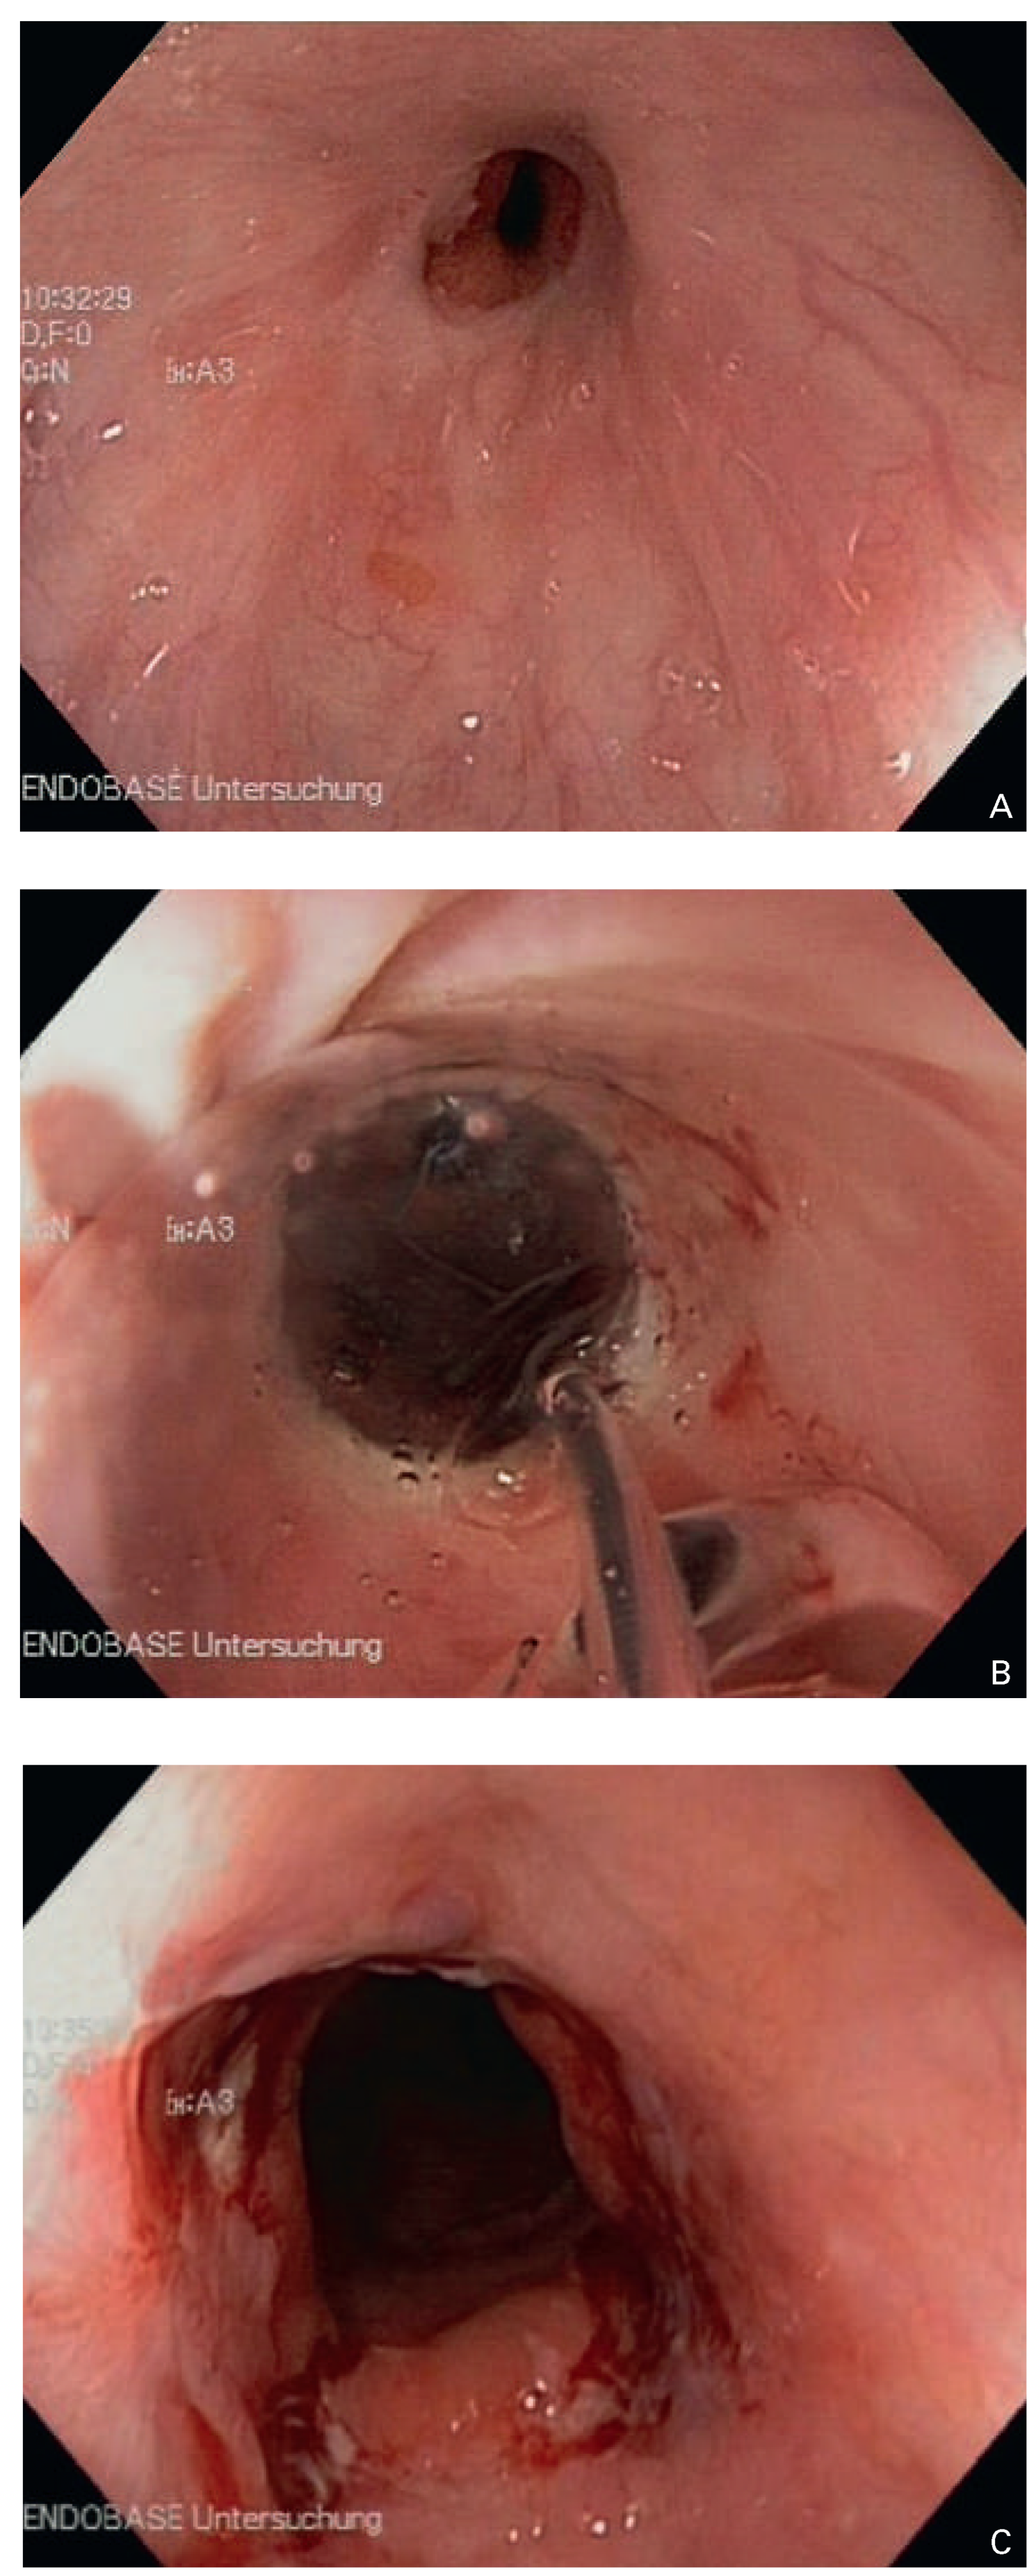

Die Inzidenz der ösophagealen Tumoren, insbesondere des Adenokarzinoms des distalen Ösophagus, ist im Zunehmen begriffen. Unbehandelt bewirken diese Neoplasien rasch eine Einengung des ösophagealen Lumens, welche für das Leitsymptom der Dysphagie verantwortlich ist. Dementsprechend ist die Passage des TEE-Gerätes of stark erschwert bis verunmöglicht, was das Perforationsrisiko erhöht. Auch nach Behandlung der Neoplasie bleibt ein Risiko bestehen. Die chirurgische Resektion geht mit einer tiefgreifenden Alteration der Anatomie einher. Zudem ist sie mit dem Risiko einer Anastomosenstenose behaftet, welche klinisch bisweilen unterschätzt wird, weil die Betroffenen von ihrem präoperativen Zustand her an ein gewisses Ausmass an Dysphagie gewöhnt sind. Therapeutisch können solche Stenosen mit endoskopischer Ballondilatation angegangen werden (Abb. 2A–C). Nach kurativ intendierter oder palliativer Radiotherapie steht das Risiko einer Strahlenösophagitis (vgl. unten), mit oder ohne Stenosierung, einer TEE entgegen. Ein häufiger palliativer Therapieansatz ist die Ösophagusstent-Einlage. Damit kann zwar die Tumorstenose effektiv überbrückt und die Dysphagie weitgehend behoben werden; dennoch wäre eine TEE – so es in diesem Kontext überhaupt sinnvolle Indikationen gibt – wegen der manipulationsbedingten Stent-Dislokationsgefahr kontraindiziert.

Abbildung 2. Ösophagoskopischer Befund bei Anastomosenstenose nach Ösophagusteilresektion. (A) Ösophagogastrische Anastomose, (B) endoskopische Ballondilatation, (C) Resultat nach Ballondilatation